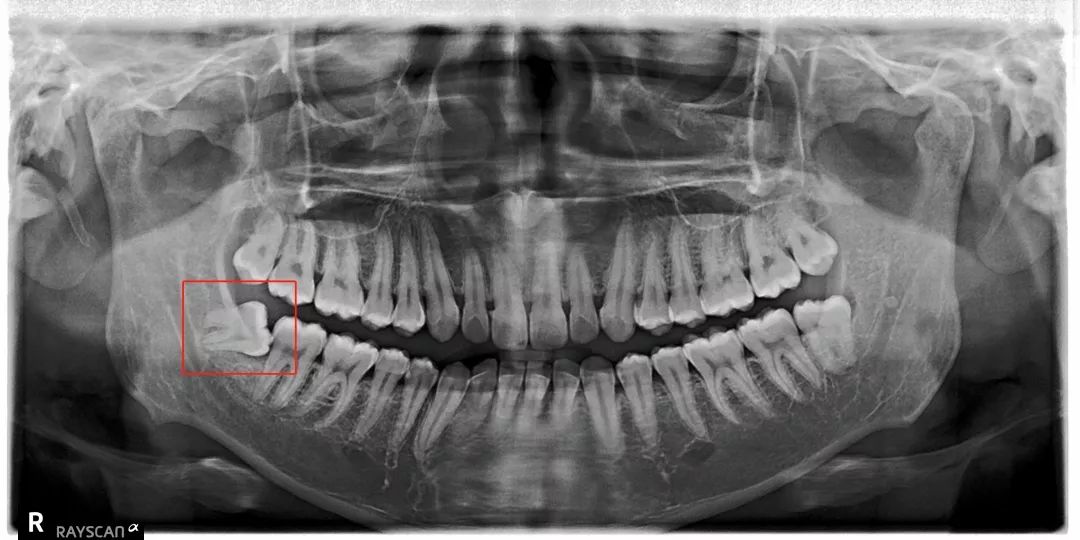

但是有部分智齿会顽强抵抗

比方说像树根一样长出很多「根」

扎根在骨头里,死死抓住

➋ 挖地三尺